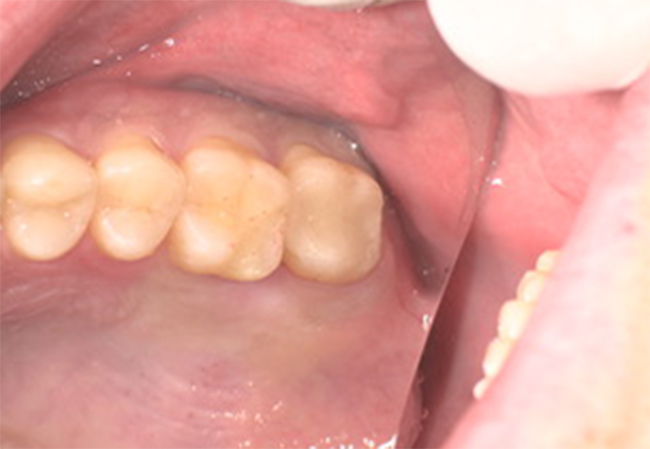

Before①

年齢・性別

29歳男性

主訴

銀歯を換えたい

診査診断

審美障害

治療計画

セレックによるセラミック治療

治療期間・金額

1日2回 ¥33,000

リスク

知覚過敏、歯ぎしり等による破折